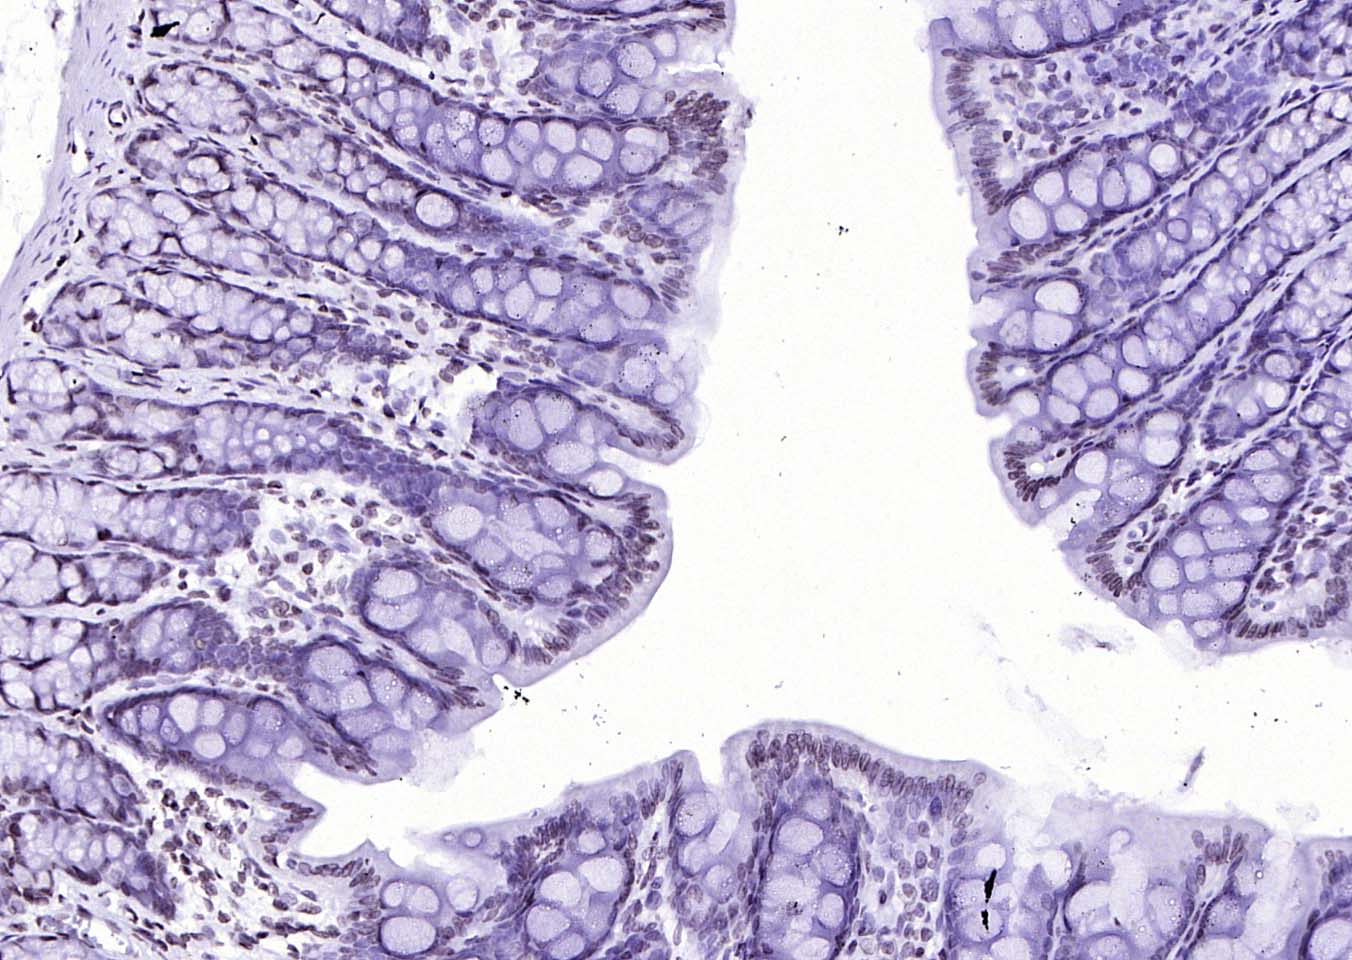

Paraformaldehyde-fixed, paraffin embedded (mouse colon); Antigen retrieval by boiling in sodium citrate buffer (pH6.0) for 15min; Block endogenous peroxidase by 3% hydrogen peroxide for 20 minutes; Blocking buffer (normal goat serum) at 37°C for 30min; Antibody incubation with (MYB) Polyclonal Antibody, Unconjugated (bs-5978R) at 1:200 overnight at 4°C, followed by operating according to SP Kit(Rabbit) (sp-0023) instructionsand DAB staining.